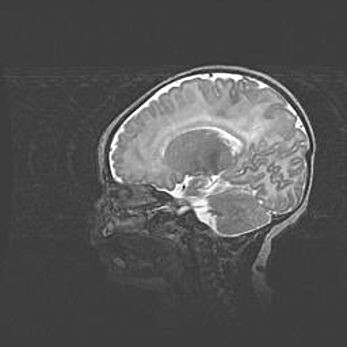

Аномалия Денди-Уокера. Признаки гипоплазии мозолистого тела.

Возраст: 5 месяцев 3 дня

Вес: 5550 г

Пол: мужской

Окружность головы: 39 см

Срок гестации: 40 недель

Аномалия Денди-Уокера – это порок развития головного мозга, для которого характерна триада симптомов: гипотрофия или аплазия червя мозжечка и/или полушарий мозжечка, расширение четвёртого желудочка с формированием ликворной кисты задней черепной ямки, гипертензионная гидроцефалия различной степени.

Гипоплазия мозолистого тела относится к дефектам внутриутробного этапа развития мозговой ткани, возникающим в процессе закладки структур головного мозга, что происходит на начальных этапах развития эмбриона.